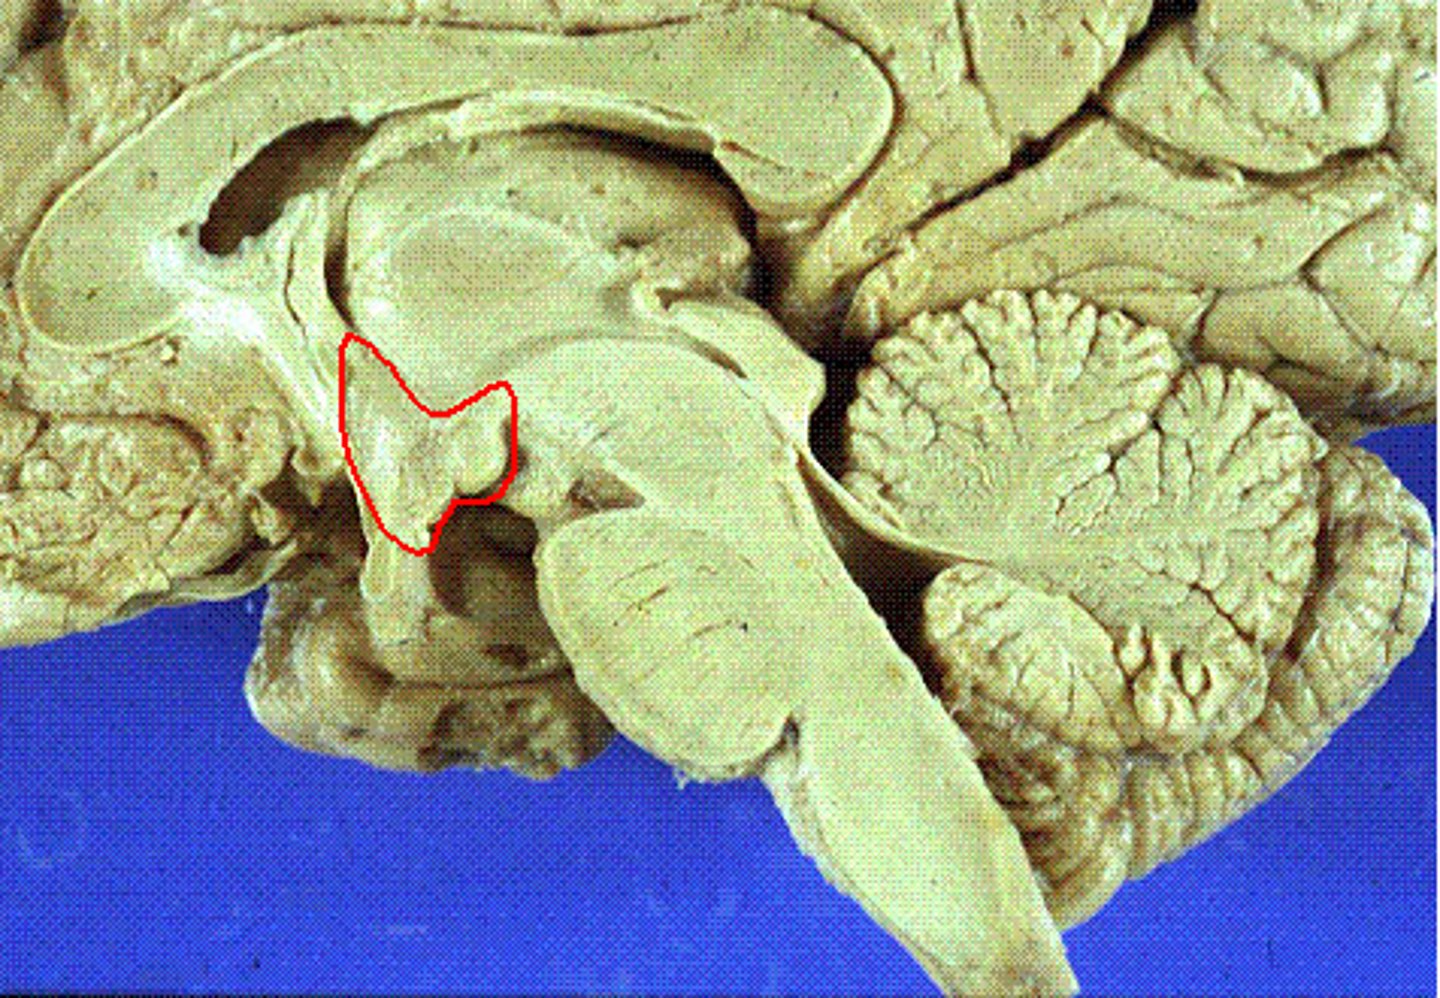

Cerebellum

Part of the brain which controls voluntary functions and motor skills such as coordination

Midbrain

Bridge which connects forebrain and hindbrain. Also processes visual and auditory information and helps with motor control

Corpus Callosum

Part of the limbic system. Band of nerve fibers which connect the 2 hemispheres of the brain